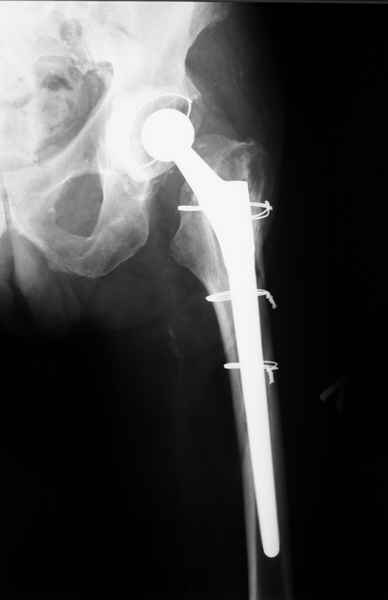

2. Применение ножки дистальной фиксации, мы отдаем предпочтение ножке Вагнера с фиксацией проксимального отдела на ножке. Более травматичное вмешательство, но при стабильной фиксации ножки реабилитация идет в обычном режиме.

Хочется показать два подобных случая, П-ка Зубарева 72 лет и п-т Гладковский 80 лет. Сразу принимаю замечание, что это были ножки цементной фиксации, просто под руками не было бесцементника.